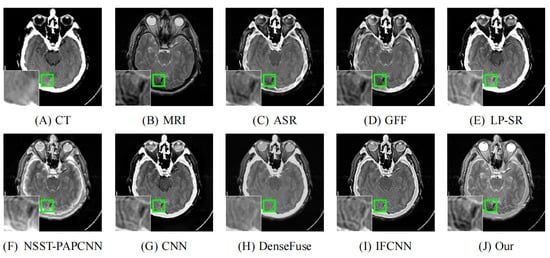

Inspired by previous works, we propose a fusion strategy, which is based on the visual saliency-based method (VSM) [34]. We use VSM to calculate the weight maps of computed tomography (CT) images. Then, based on these CT image weight maps we obtain the weight maps of magnetic resonance imaging (MRI) images. Figure 1 presents the visual saliency map of CT image on the image pair “Acute stroke speech arrest-3”. It is obviously observed that VSM of CT can remain the features of dense structures such as implants and bones. Meanwhile, the low-resolution soft tissues are reduced.

Figure 1. Example of a CT image and its visual saliency map. (a) The source CT image of “Acute stroke speech arrest-3”. (b) The visual saliency map of this CT image.

Figure 8. Fusion images of “Acute stroke speech arrest-7” by various methods. From (A) to (J): CT, MRI, ASR, GFF, LP-SR, NSST-PAPCNN, CNN, DenseFuse, IFCNN, Our proposed method.